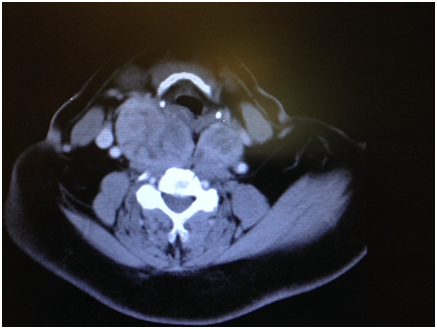

Figure 1 CT scan soft tissue neck showing enlarged thyroid displacing carotid artery on the right side.